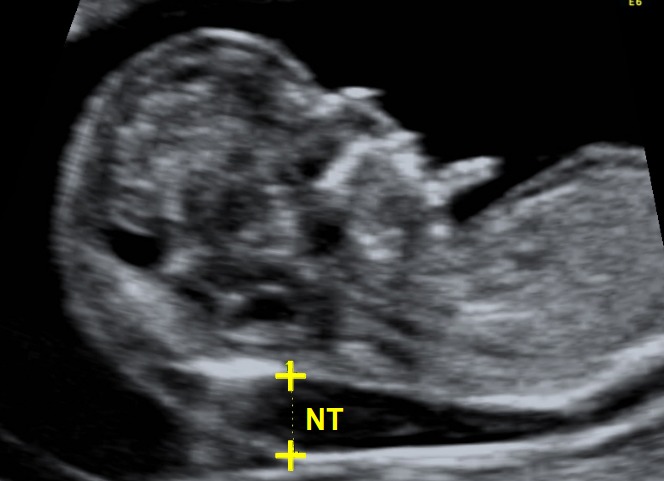

Độ mờ da gáy là gì?

Độ mờ da gáy (Nuchal Translucency – NT) là một khoảng dịch dưới da ở vùng gáy của thai nhi, có thể quan sát được qua siêu âm trong tam cá nguyệt đầu tiên.

Đây là một chỉ số quan trọng giúp bác sĩ đánh giá nguy cơ mắc dị tật bẩm sinh, đặc biệt là hội chứng Down và một số bất thường nhiễm sắc thể khác.

Hình dung đơn giản, độ mờ da gáy giống như một lớp chất lỏng nằm ở phía sau cổ thai nhi. Khi đo chỉ số này, bác sĩ sẽ sử dụng siêu âm đo độ mờ da gáy để xác định độ dày của vùng dịch này.

Việc đo độ mờ da gáy được thực hiện bằng phương pháp siêu âm thai trong khoảng tuần 11 – 13 của thai kỳ. Quy trình cụ thể như sau:

Bước 2: Tiến hành siêu âm đo độ mờ da gáy

- Bác sĩ sử dụng đầu dò siêu âm đặt trên bụng mẹ để quan sát vùng gáy thai nhi.

- Khi hình ảnh thai nhi hiển thị rõ ràng, bác sĩ sẽ đo khoảng sáng sau gáy (vùng dịch dưới da sau gáy thai nhi) và ghi lại chỉ số.